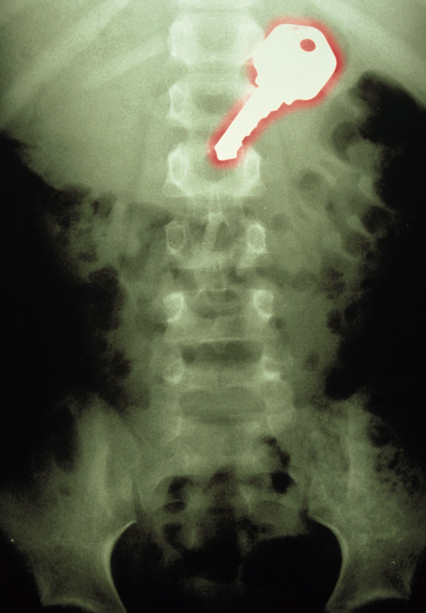

7) Lo que ves a continuación, es el Rayo X de un niño de 7 años que se tragó una llavecita… ¡Ouch!

Barcroft | The Telegraph